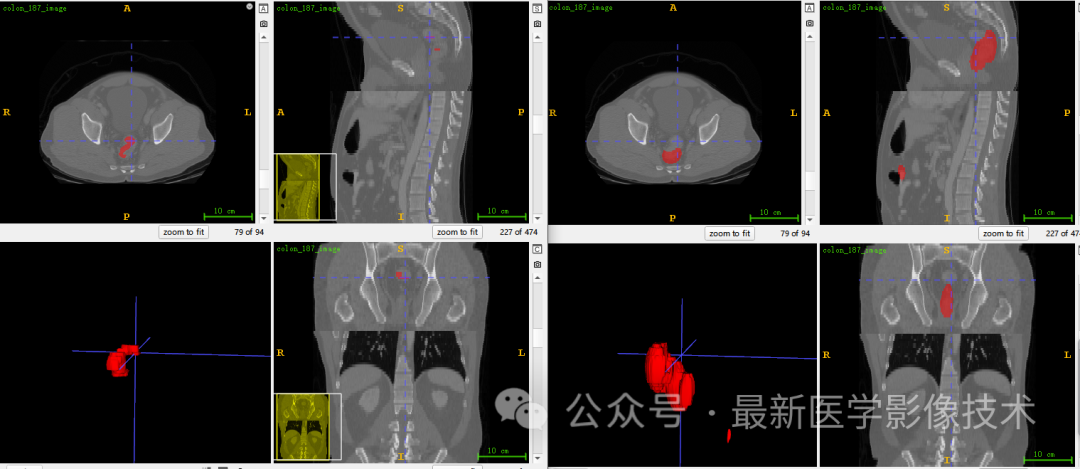

5、验证集分割结果

左图是金标准结果,右图是预测结果。